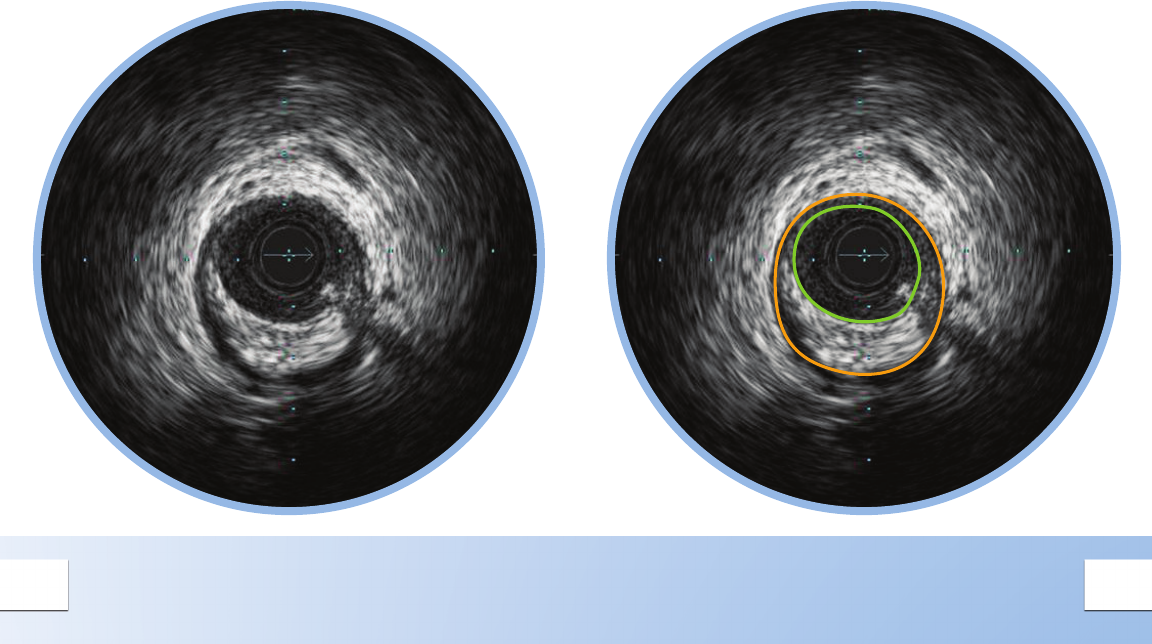

ECCENTRIC MIXED PLAQUE

Eccentric plaques are distributed non-

circumferentially in the vessel; this makes the

assessment of disease by angiography especially

prone to underestimation or overestimation

depending on the angle of view.

Side

Branch

Branch Acoustic

Shadowing

Calcium is indicated by very bright areas with

acoustic shadowing that blocks out the image

behind. This shadowing occurs because the high

density of calcium dampens the ultrasound echo.

Nearby vessels on the periphery can be seen

moving in and out of the eld of view and can be

used as landmarks.